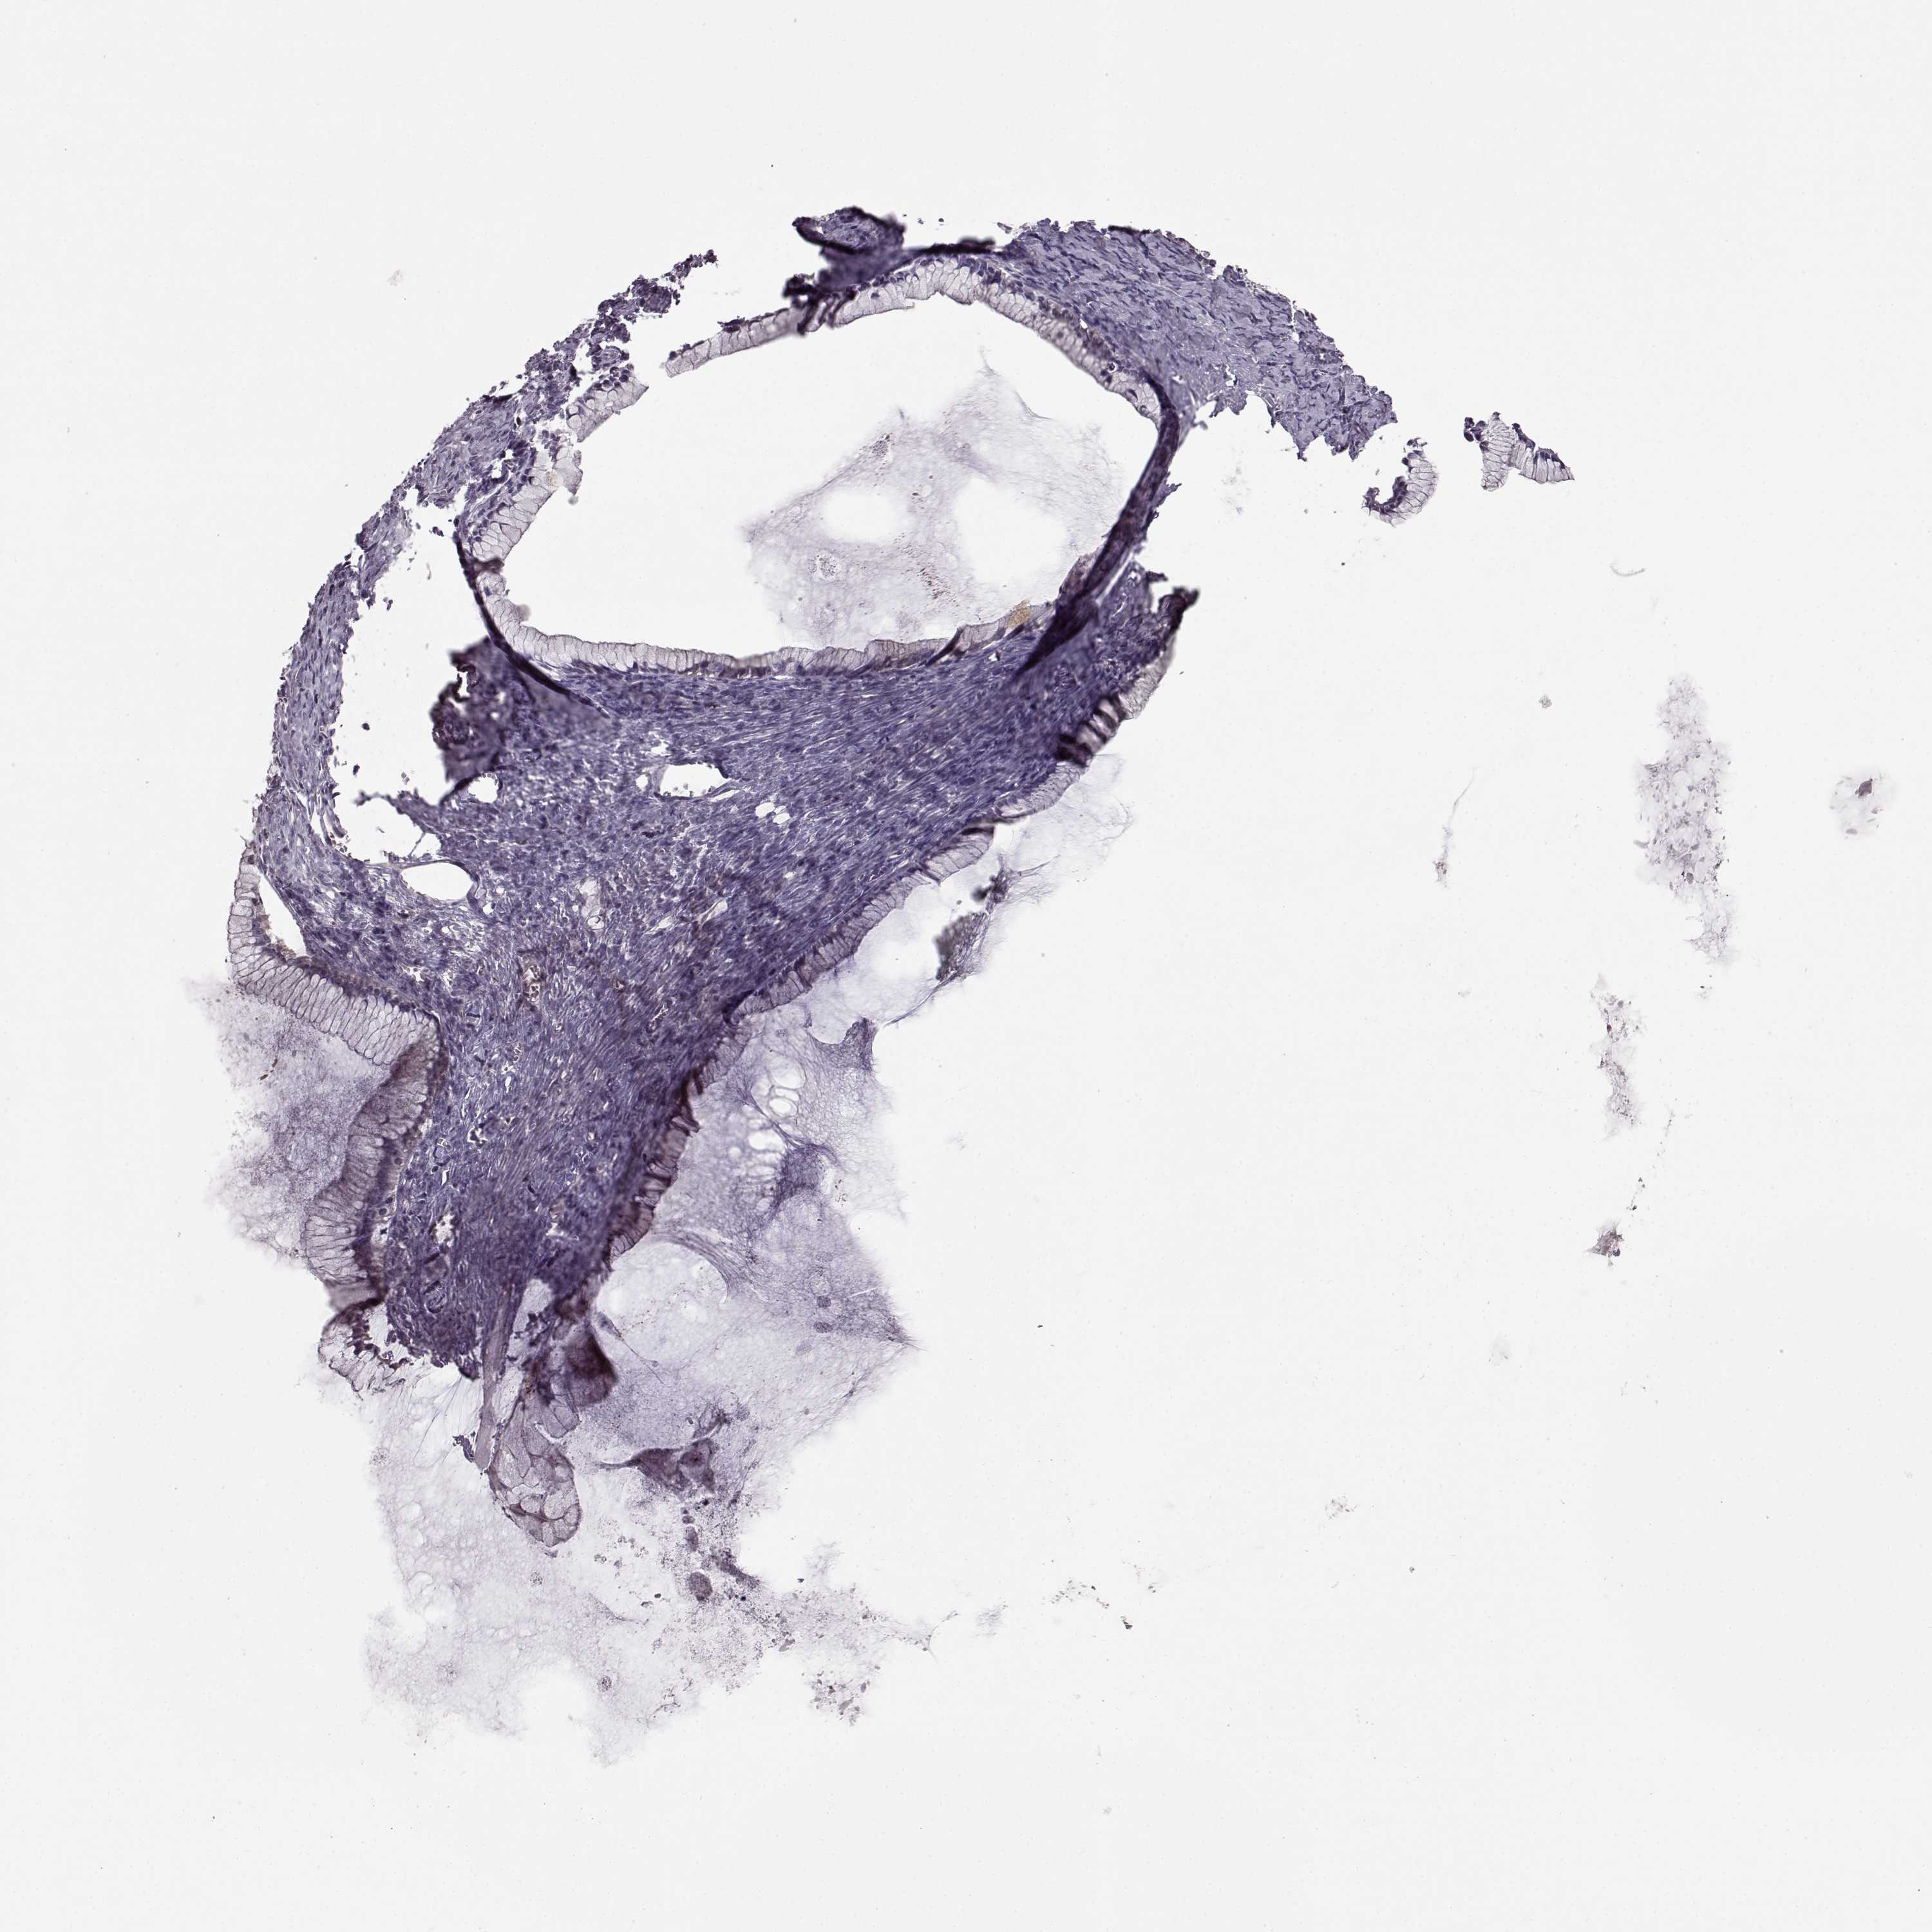

OVARIAN CANCER - Protein expressioni

A mouse-over function shows sample information and annotation data. Click on an image to view it in a full screen mode. Samples can be filtered based on level of antibody staining by selecting one or several of the following categories: high, medium, low and not detected. The assay and annotation is described here.

Note that samples used for immunohistochemistry by the Human Protein Atlas do not correspond to samples in the TCGA dataset.

Antibody stainingi

Antibody staining in the annotated cell types in the current human tissue is reported as not detected, low, medium, or high, based on conventional immunohistochemistry profiling in selected tissues. This score is based on the combination of the staining intensity and fraction of stained cells.

Each image is clickable and will lead to virtual microscopy that enables deeper exploration of all samples and also displays staining intensity scores, fraction scores and subcellular localization as well as patient and tissue information for each sample.

Antibody HPA069703

Antibody CAB023410

Staining

High

Medium

Low

Not detected

Intensity

Strong

Moderate

Weak

Negative

Quantity

>75%

75%-25%

<25%

None

Location

Nuclear

Cytoplasmic/membranous

Cytoplasmic/membranous,nuclear

Cystadenocarcinoma, serous, NOS

Cystadenocarcinoma, mucinous, NOS

Carcinoma, endometroid